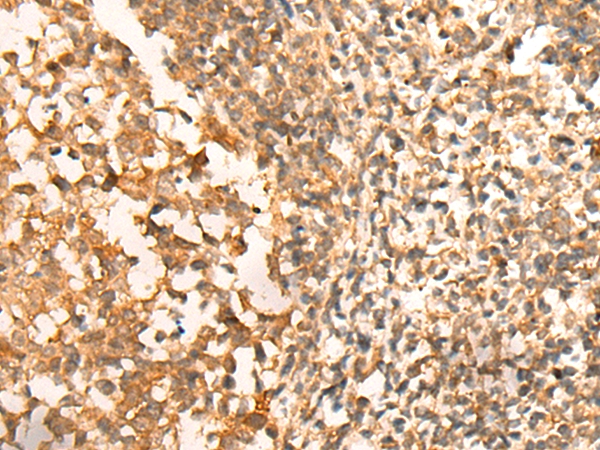

The image on the left is immunohistochemistry of paraffin-embedded Human colorectal cancer tissue using 46476(CEP57 Antibody) at dilution 1/30, on the right is treated with fusion protein. (Original magnification: x200)